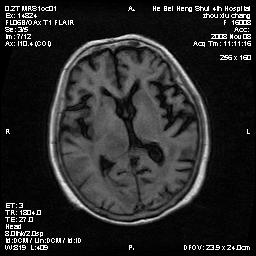

标题: MRI1883:女67岁,半年前曾患脑梗塞,治疗后好转,近3各月精 [打印本页]

女67岁,半年前曾患脑梗塞,治疗后好转,近3各月精神恍惚。

形态及整体病灶看起来首先考虑转移瘤或淋巴瘤,但奇怪的是多个病灶周围均未见显著的水肿区,这不符合这两个肿瘤的特点,结合ct表现及患者病史有个人考虑是否有皮层下动脉硬化性脑病伴多发胶质增生可能.

考虑  皮层下动脉硬化性脑病伴脑炎或

不像占位性病变,考虑脱髓鞘改变